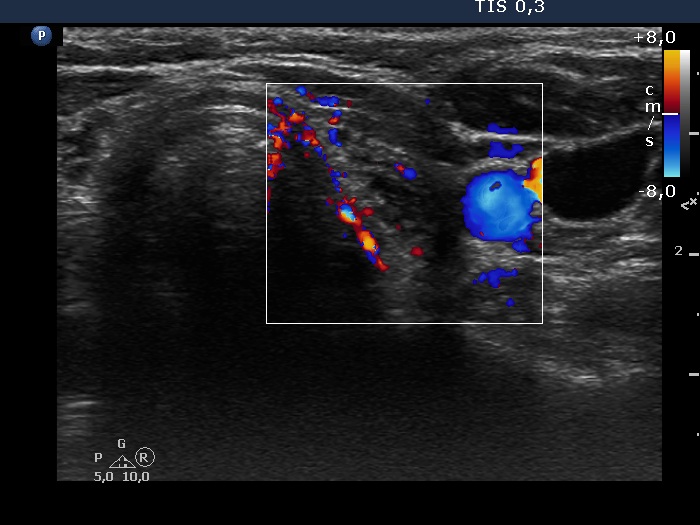

Consecutive patients with the final diagnosis of Hashimoto's thyroiditis - case 58 (1576) (ultrasonographic picture 6)

Left lobe, transverse view, color Doppler mode. The vascularization is not specific.